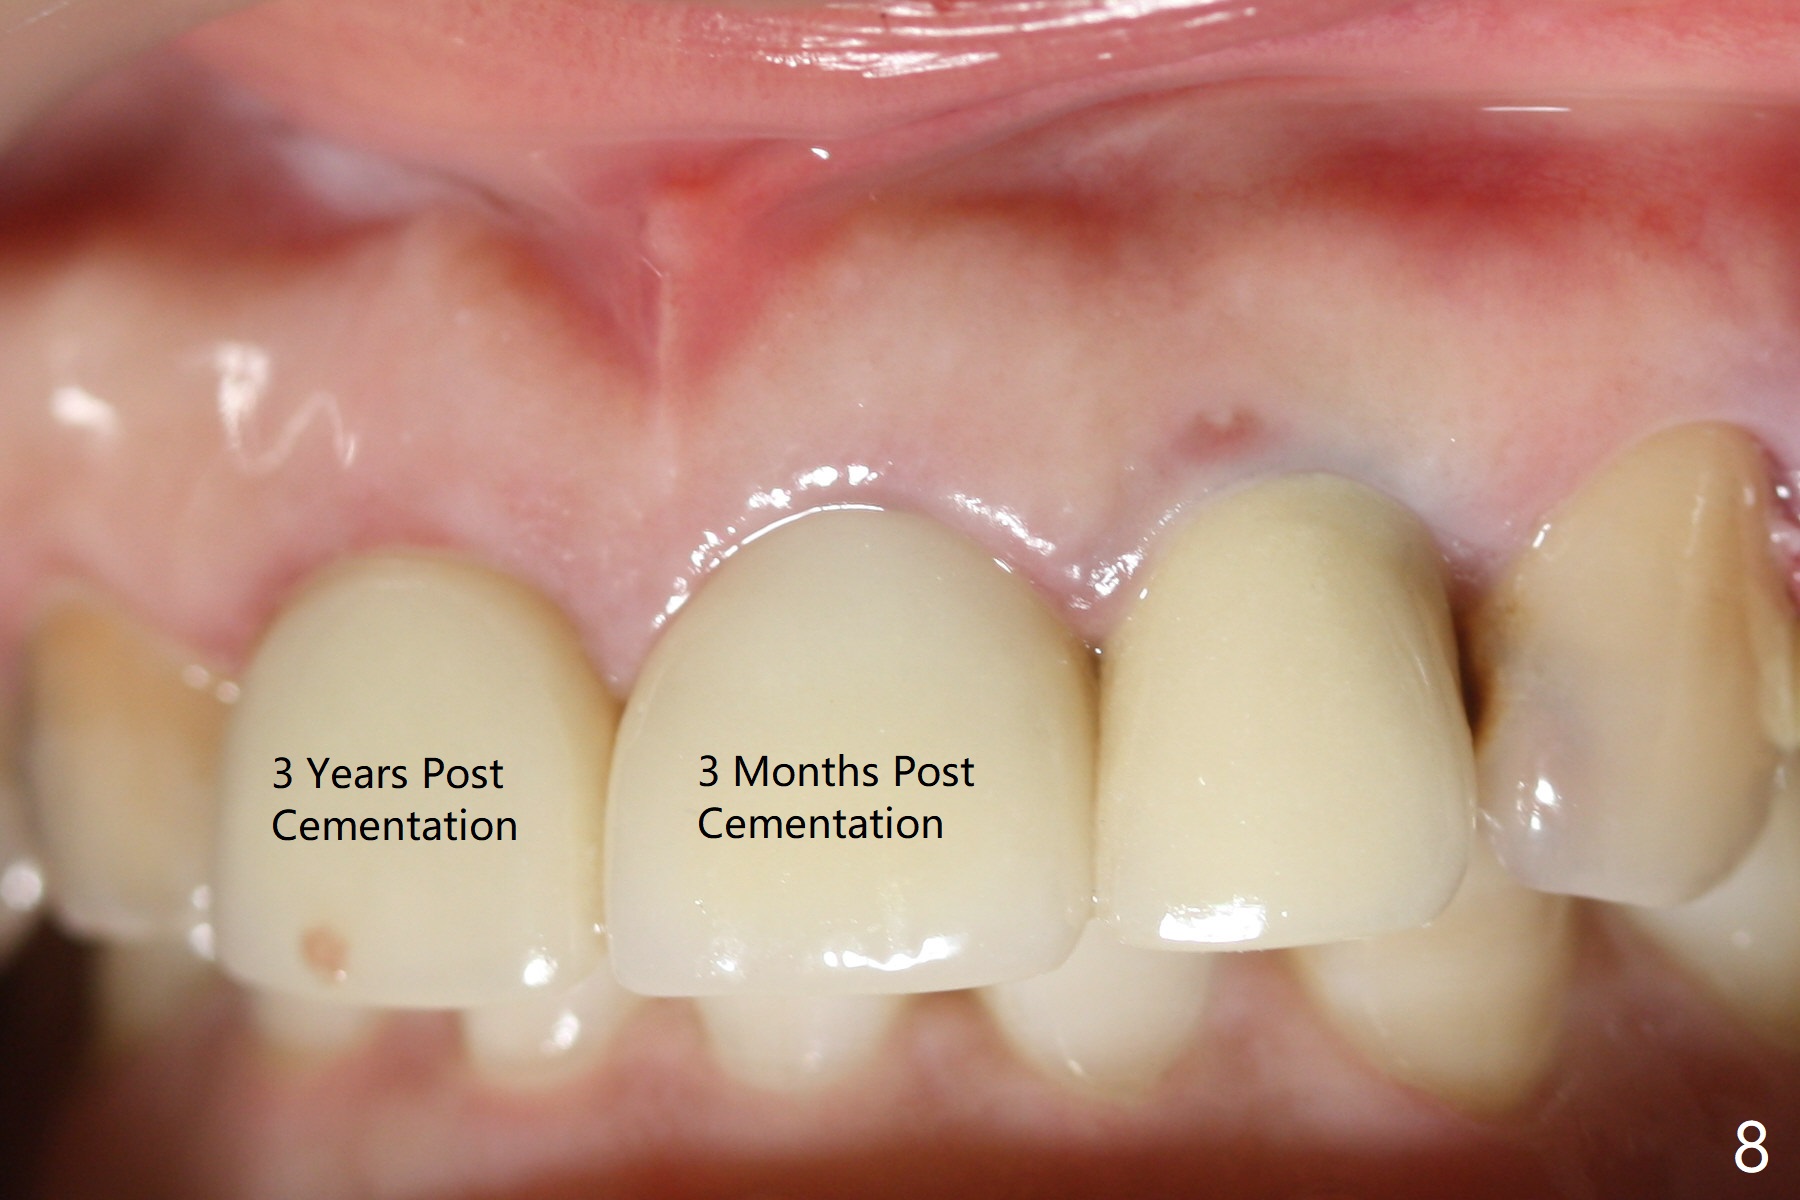

When the 44-year-old woman returns, the crown dislodges from #9 with palatal porcelain chip (Fig.1). Although the post is in place as compared to its dislodgement last visit, it is short and pointed (Fig.2,3 P). Because of the anterior deep bite (Fig.4), an implant restoration may not provide advantage; a new build-up is fabricated (B-U) for a new crown (Fig.5-6). The existing crown is reinserted for shade comparison (Fig.7 C). The gingiva at #8 and 9 is healthy, whereas that at #10 is not (Fig.8). PA taken 5 months later shows that the crown at #10 looks normal (Fig.9).